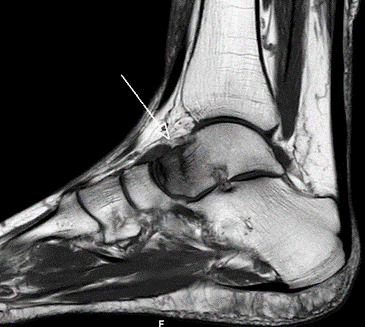

Bei Verschlechterung des Befundes erfolgte nach nunmehr 9 Wochen nach dem Unfall eine MRT Untersuchung, bei der sich ein unverschobener Bruch des Sprungbeinhalses ergab. (Abb. 3)

Abb. 3 MRT 9 Wochen nach dem Unfall